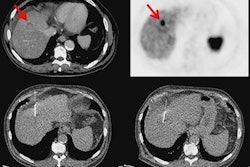

Maximum-intensity projection images with Cu-64 DOTATATE PET/CT are from a patient with metastatic bronchial carcinoid and extensive metastatic disease, including multiple small liver metastases (A). Corresponding CT image (B), PET (C), and fused PET/CT (D) show multiple bone metastases (yellow arrows). Images courtesy of JNM.Cu-64 DOTATATE prompted only a handful of minor adverse effects. Five (8%) of the 63 subjects reported a total of nine mild to moderate adverse events, with eight of those incidents deemed "probably" not related to the radiotracer. The complaints included one case each of nausea, headache, and fainting, along with two cases of vomiting.